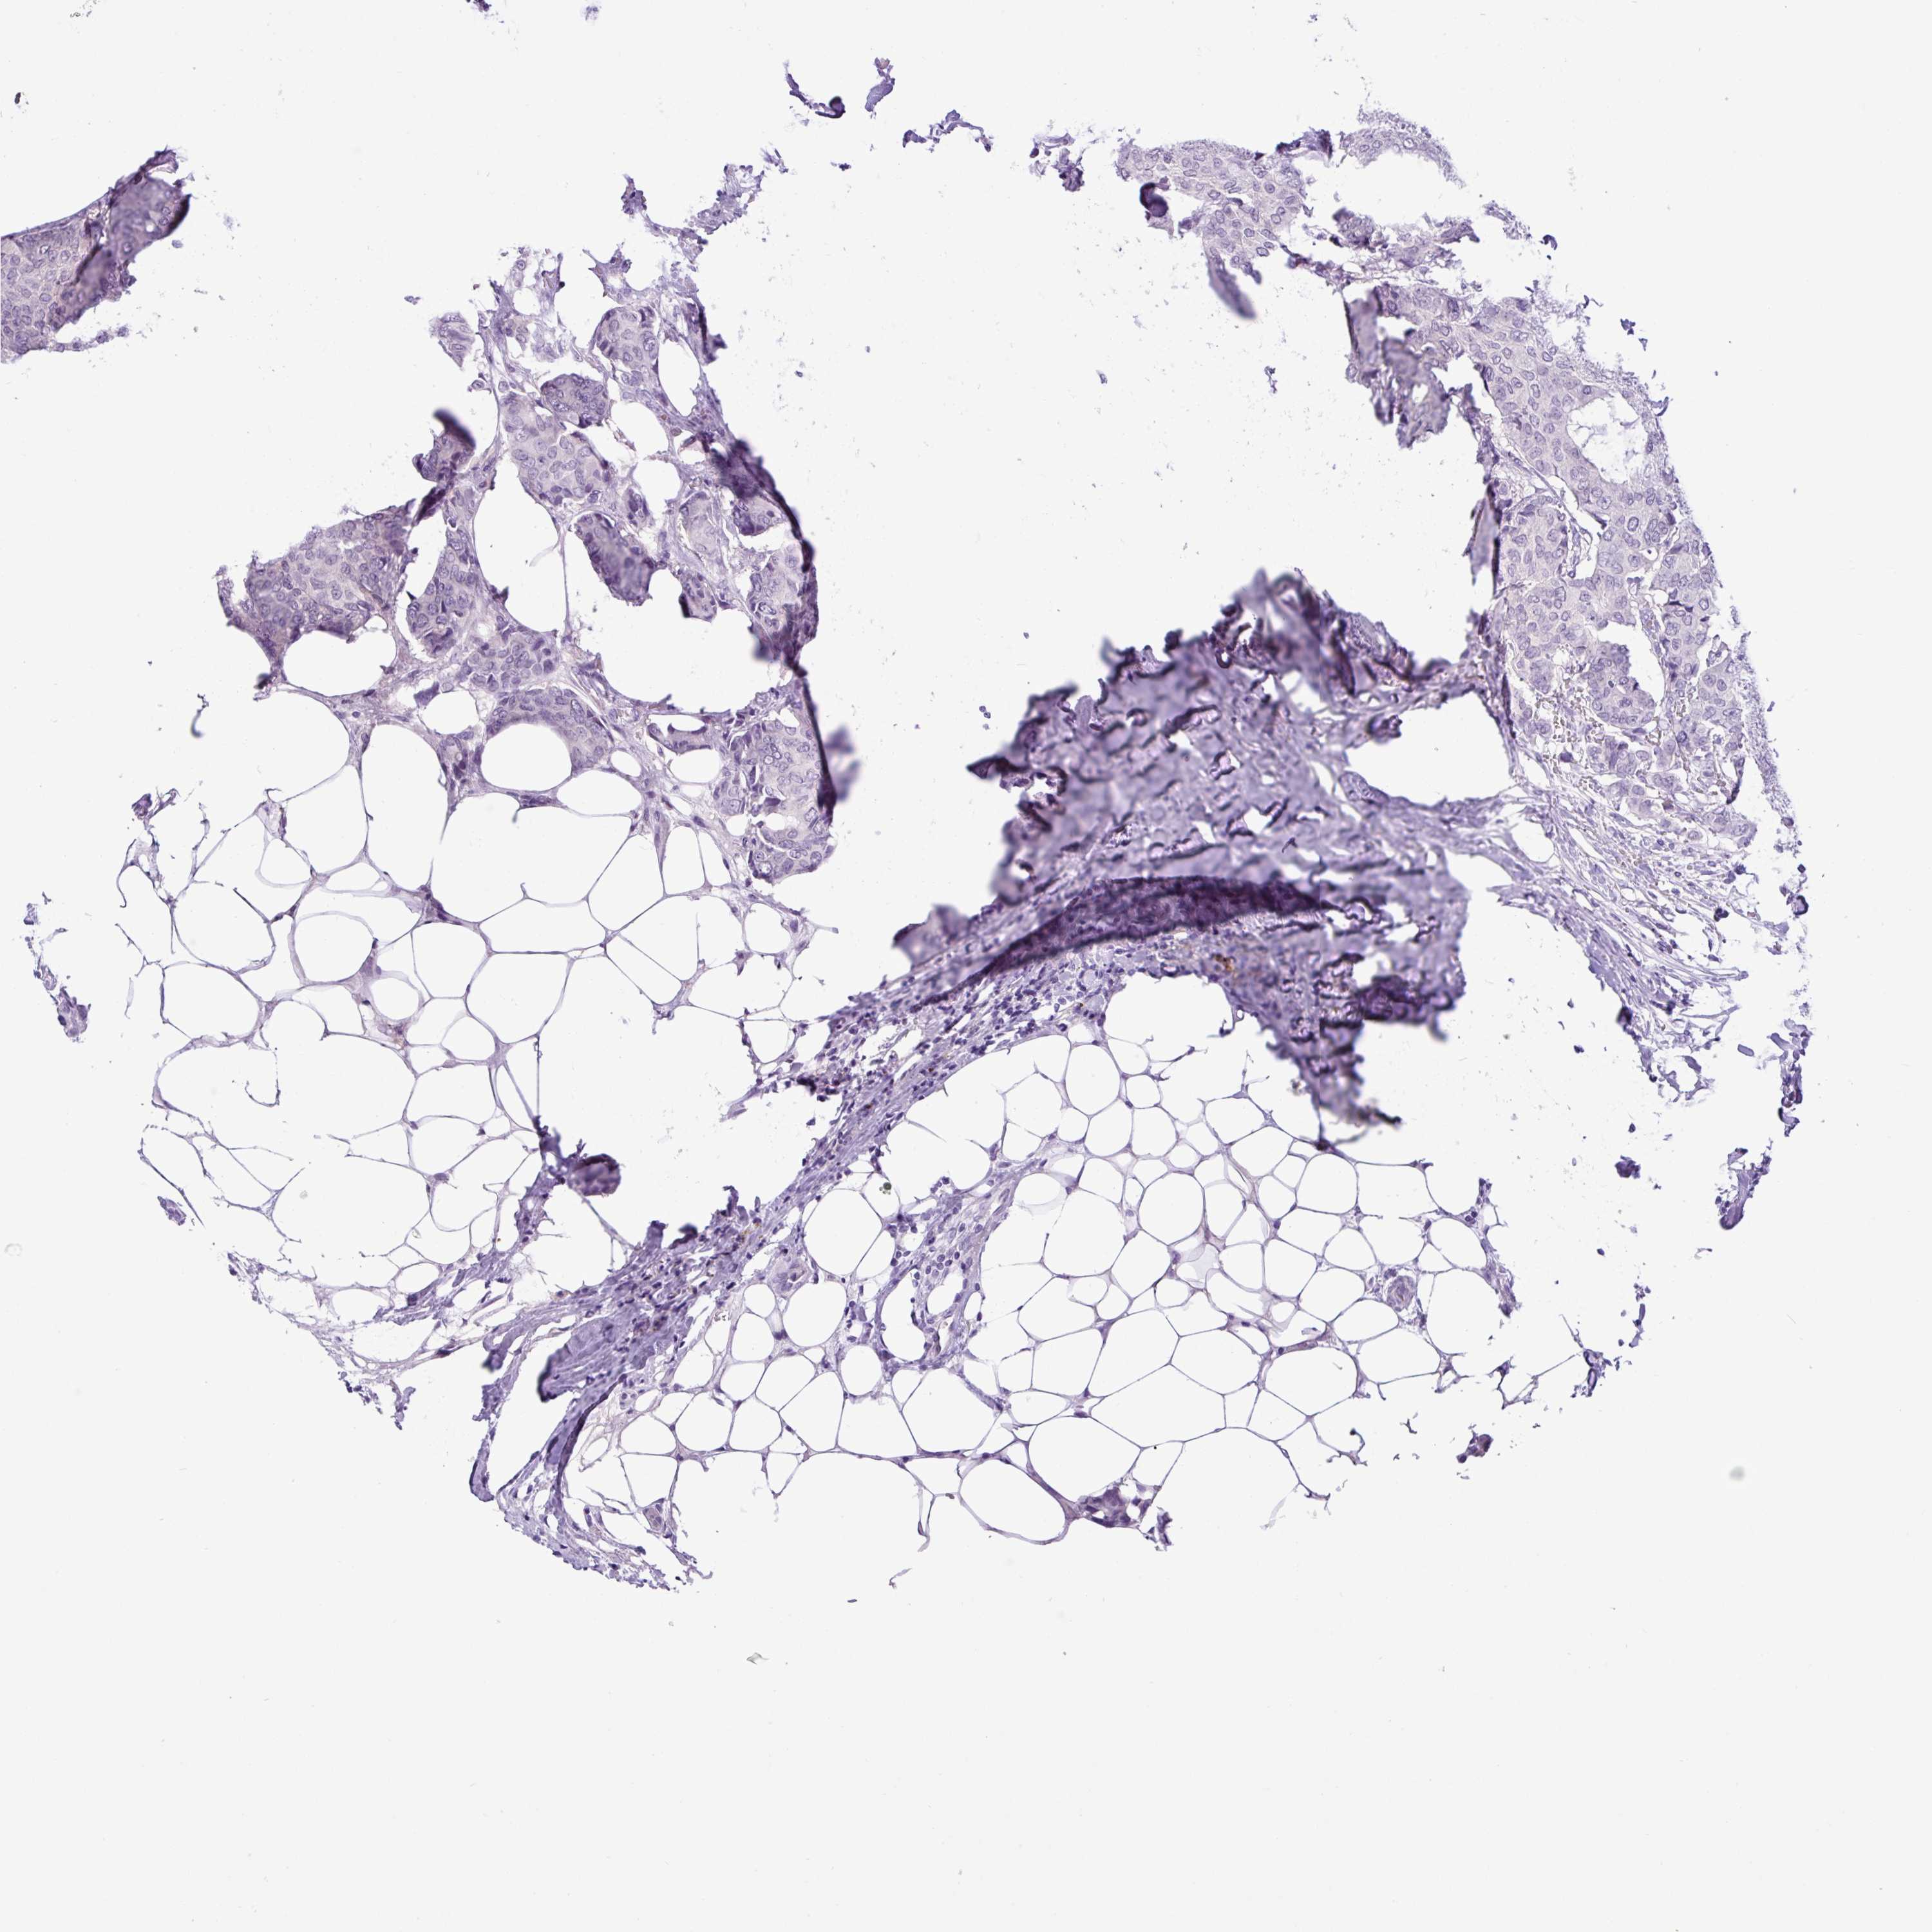

Breast cancer

Human cancer